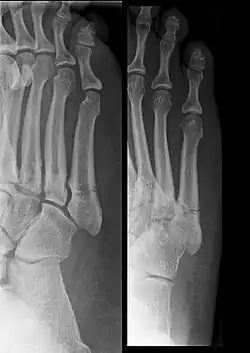

Bei der Jones-Fraktur handelt es sich um einen basisnahen Knochenbruch des 5. Mittelfußknochens im proximalen meta-diaphysären Übergang ohne Beteiligung des tarsometatarsalen Gelenks (meist aber des intermetatarsalen Gelenkes zum Metatarsale 4). Diese Fraktur ist seltener als die Abrissfraktur an der Tuberositas mit Gelenkbeteiligung, jedoch ist die Gefahr eines Nichtverheilens (Pseudarthrose) deutlich höher, vor allem bei konservativer Therapie.[1]

Die Jones-Fraktur verläuft im meta-diaphysären Übergang quer zur Schaftachse etwa 1,5 bis 2 cm distal des tarsometatarsalen Gelenks, das nicht beteiligt ist. Dieser Bereich ist schlecht durchblutet, was die Ausbildung von Pseudarthrosen begünstigt. Der Bruch ist fast nie verschoben (disloziert). Oftmals werden auch andere Brüche der Basis des fünften Mittelfußknochens als „Jones-Fraktur“ oder als „Pseudo-Jones-Fraktur“ bezeichnet. Eine Einteilung der Knochenbrüche des fünften Mittelfußknochens wurde von Dameron und Quill 1995 vorgeschlagen:

- Dameron-Quill Typ 1: Abriss der Tuberositas (avulsion fracture, Pseudo-Jones’ fracture, dancer’s fracture)

- Dameron-Quill Typ 2: Fraktur im meta-diaphysären Übergang (true Jones’ fracture)

- Dameron-Quill Typ 3: Stressfraktur des proximalen Schafts

- Dameron-Quill Typ 4: distale Frakturen von Schaft, Hals oder Kopf